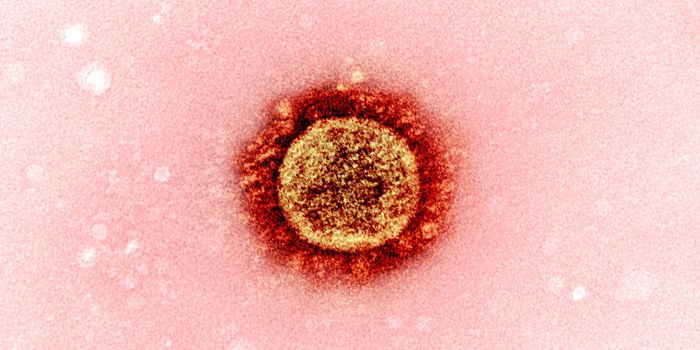

DEC 24, 2020MicrobiologyThe UK recently reported that it had detected a new variant of the SARS-CoV-2 pandemic virus, which causes COVID-19. Thi ...